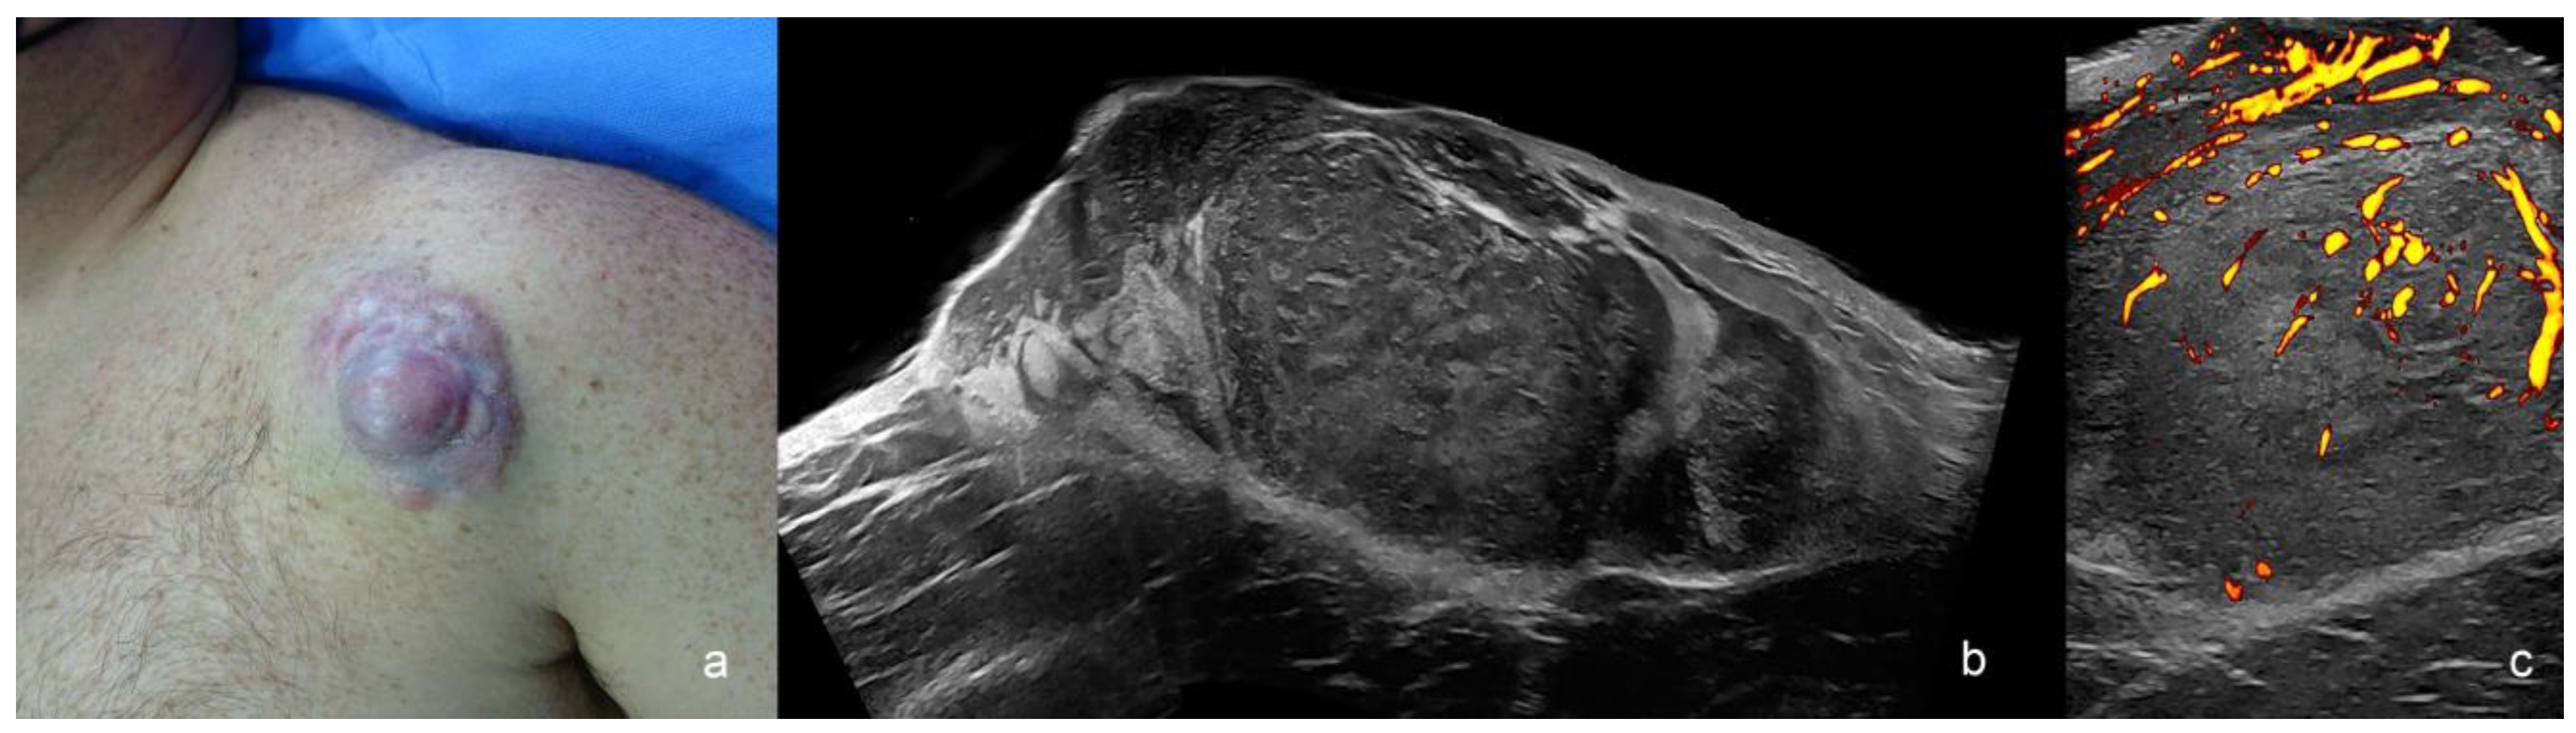

Primary SCC Tumor

| Squamous Cell Carcinoma | hypoechoic, crumpled, wavy or irregular epidermis, convex, concave flat, bulging or fusiform shape, irregular borders | intermediate degree |